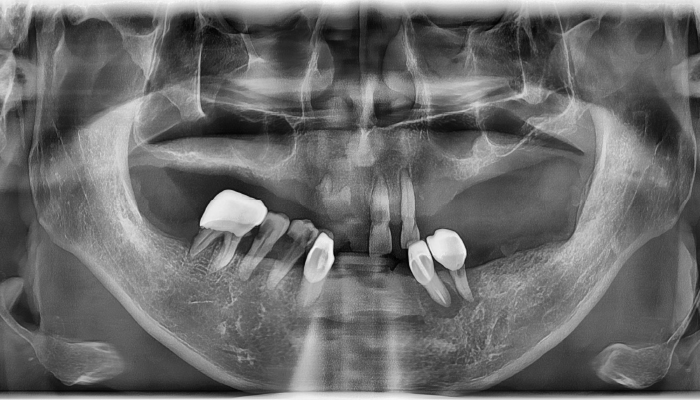

• 식립 전

식립 후